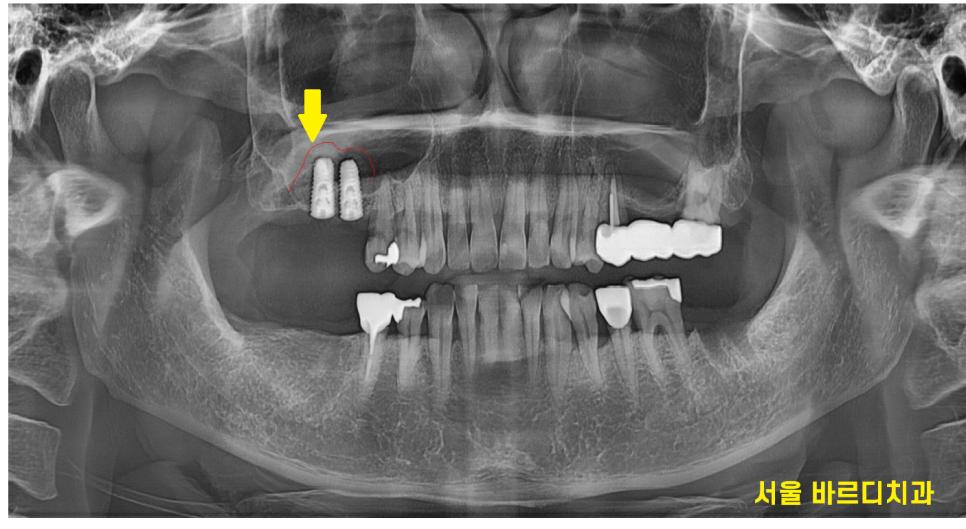

상악동 거상술은 상악동을 살짝 들어 올려

임플란트를 심을 수 있는 공간을 확보하는 시술인데..

이 상악동이 굉장히 얇습니다.

힘을 조금만 잘못 주어도 상악동을 터트릴 수 있고

임플란트가 상악동 내부로 들어갈 수 있기 때문에

내려온 상악동을 위로 올려주고

그 사이에 뼈를 채워주면서 수술이 진행됩니다.

ct를 확인하면 미사 임플란트 시 이식된 뼈이식

확인이 가능하죠~